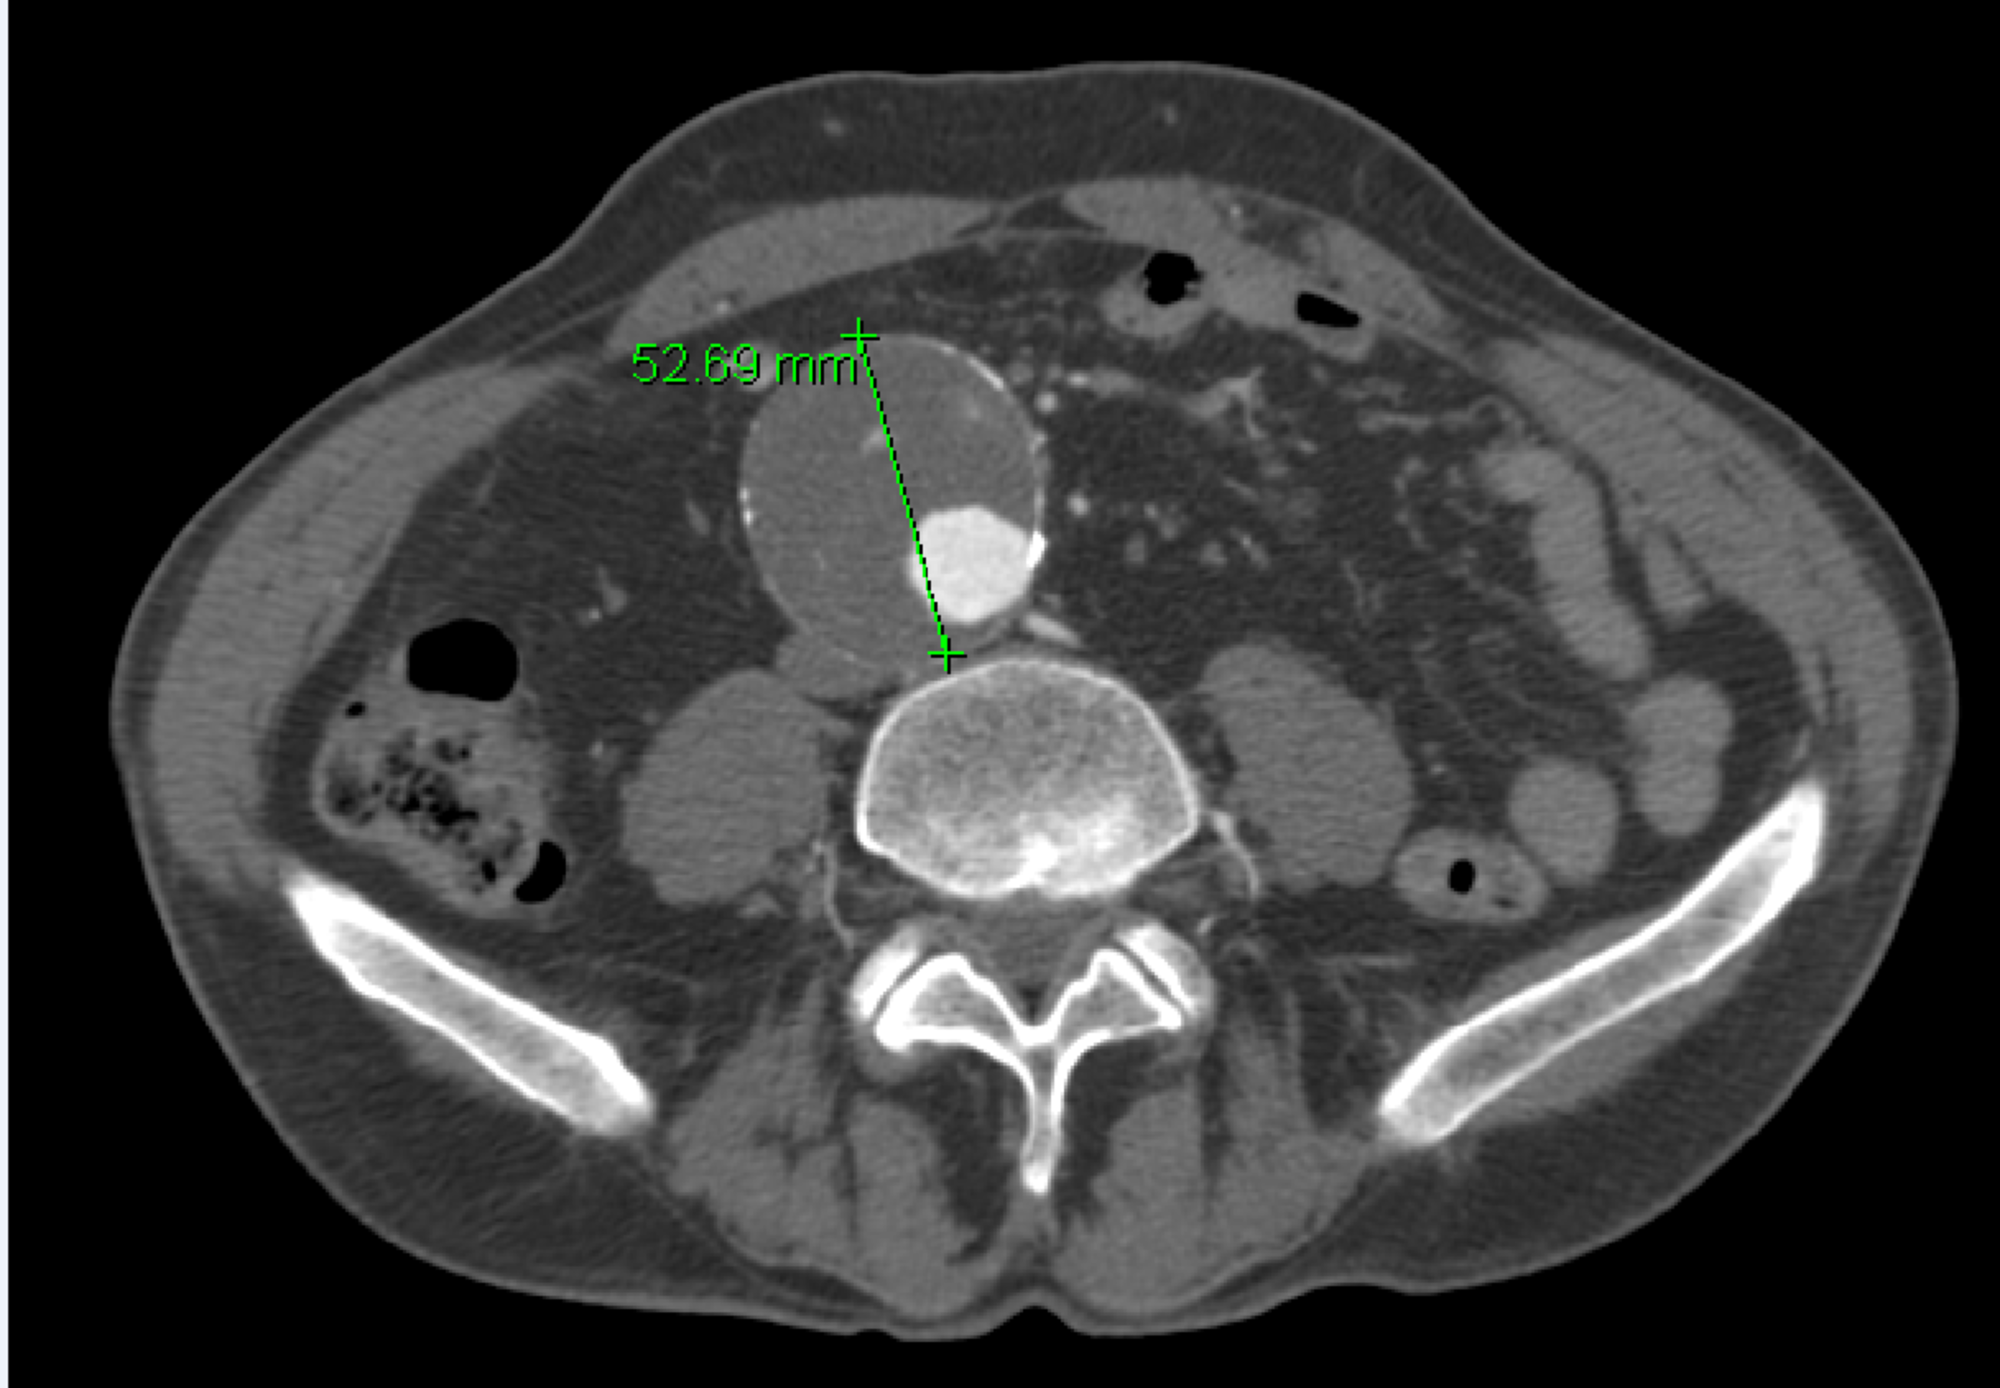

EVAR Approach for Abdominal Aortic Aneurysm with Horseshoe Kidney A Horseshoe Kidney Aaa Horseshoe kidney (hsk) is a rare congenital fusion defect and is uncommonly associated with abdominal aortic aneurysm. Horseshoe kidney (hsk), referring to the abnormal fusion of the lower renal poles, represents one of the most common renal. Ten patients with abdominal aortic aneurysms (aaas) and horseshoe kidney were treated with endovascular aneurysm repair. A systematic review of all patients that. Horseshoe Kidney Aaa.

Horseshoe kidney classification system based on the vasculature Horseshoe Kidney Aaa A systematic review of all patients that have been reported in the literature with abdominal aortic aneurysm (aaa) concomitant. Horseshoe kidney (hsk) is a rare congenital fusion defect and is uncommonly associated with abdominal aortic aneurysm. Coexistence of horseshoe kidney and abdominal aortic aneurysm (aaa) is a rare entity that presents a technical challenge to vascular. Horseshoe kidney (hsk), referring. Horseshoe Kidney Aaa.

Horseshoe kidney and AAA, with the inferior vena cava (marked by blue Horseshoe Kidney Aaa Coexistence of horseshoe kidney and abdominal aortic aneurysm (aaa) is a rare entity that presents a technical challenge to vascular. Horseshoe kidney (hsk) is a rare congenital fusion defect and is uncommonly associated with abdominal aortic aneurysm (aaa). A systematic review of all patients that have been reported in the literature with abdominal aortic aneurysm (aaa) concomitant. Horseshoe kidney (hsk). Horseshoe Kidney Aaa.